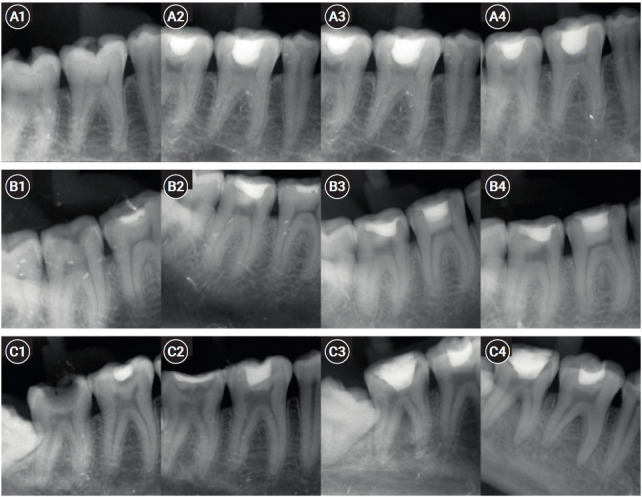

Methods: Six permanent mandibular molars with a diagnosis of symptomatic irreversible pulpitis were included. Under Local anesthesia and rubber dam isolation, caries were excavated using high-speed bur under coolant. Full coronal pulpotomy was done and hemostasis was achieved. CGF membrane was prepared and placed over the radicular pulp and layered with Biodentine (Septodont). Final restoration of type IX glass ionomer cement and bulk fill composite resin was placed. Patients were assessed for various clinical and radiographic parameters at intervals of 1 week and 3, 6, and 12 months. Five patients fulfilled the success criteria at the end of 1 year.

Results: Pulpotomy is considered an alternative treatment modality for root canal treatment in symptomatic irreversible pulpitis aiming at alleviating symptoms and maintaining vitality. CGF scaffold when used as a capping material acts as a reservoir for growth factors with anti-inflammatory properties and enhances healing.

Conclusions: Scaffold-based pulpotomy can be considered a biological approach to healing inflamed pulp.